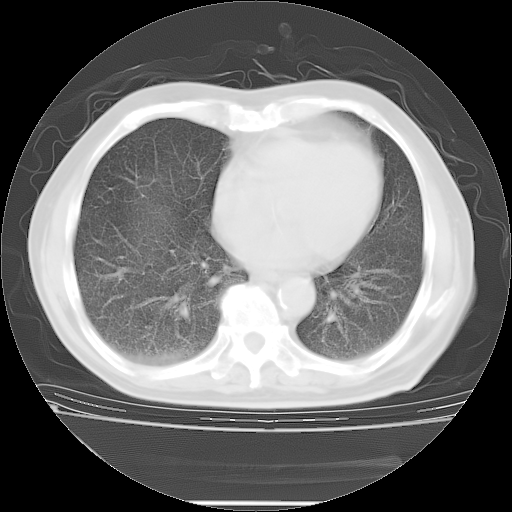

今天复查肺部CT,发现双肺广泛磨玻璃样改变。所以我把3月19日和5月9日相隔50天的肺部CT上传。请大家会诊。

5月9日肺部CT(在4月27日齐鲁医院肺部CT描述部分肺组织磨玻璃样改变,12天后肺组织广泛磨玻璃样改变)

2009年5月9日肺部CT

大致读了系列胸部CT:纵隔窗无明显异常,肺窗:从4、27至今:主要是双肺中下野外带可见毛玻璃样改变,目前处于急性肺泡炎阶段,至于原因考虑1、结替组织或胶原血管性疾病所致?2、恶性疾病如恶组在肺部所致的表现或细支气管肺泡癌?3、药物或其它原因如肺蛋白沉着症所致肺泡炎目前不太可能?总之,明天就去请我院的呼吸科、感染科、血液科和临免专家会诊哈。